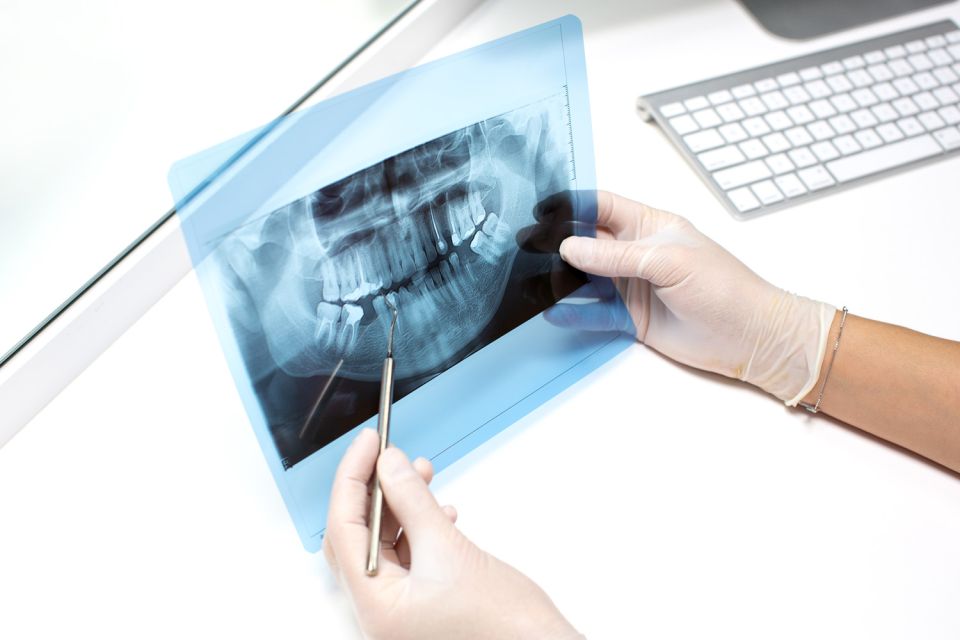

3D-Röntgendiagnostik

Bei uns sollen Sie sich sicher aufgehoben fühlen. Moderne computergestützte Röntgenverfahren, wie unser hauseigener digitaler Volumentomograph liefern ein Plus an Sicherheit und höchster Präzision bei der Diagnostik und Planung Ihrer Behandlung. Im Bereich der Implantologie ist ein Höchstmaß an Planungssicherheit gegeben, wovon der Patient direkt profitiert.

3D/DVT-Röntgen

3D/DVT-Röntgen bietet schnell und einfach die detaillierteste Information für genauere Diagnostik und mehr Präzision in Sekundenschnelle. Das DVT liefert eine vollständige Sicht der Gesichtsanatomie, nahezu aus jedem Winkel und jeder Perspektive. Eine deutliche Strahlenreduktion im Vergleich zur Computertomographie bei feinerer Schichtung der Bilder lässt den Patienten gleichsam profitieren. Es ist uns wichtig, sie bestmöglich und auf verständliche Art und Weise über alle Therapieoptionen und Risiken aufklären zu können. Genaueste Hightech-Bildgebung hilft uns dabei. Schnell-einfach-sicher!